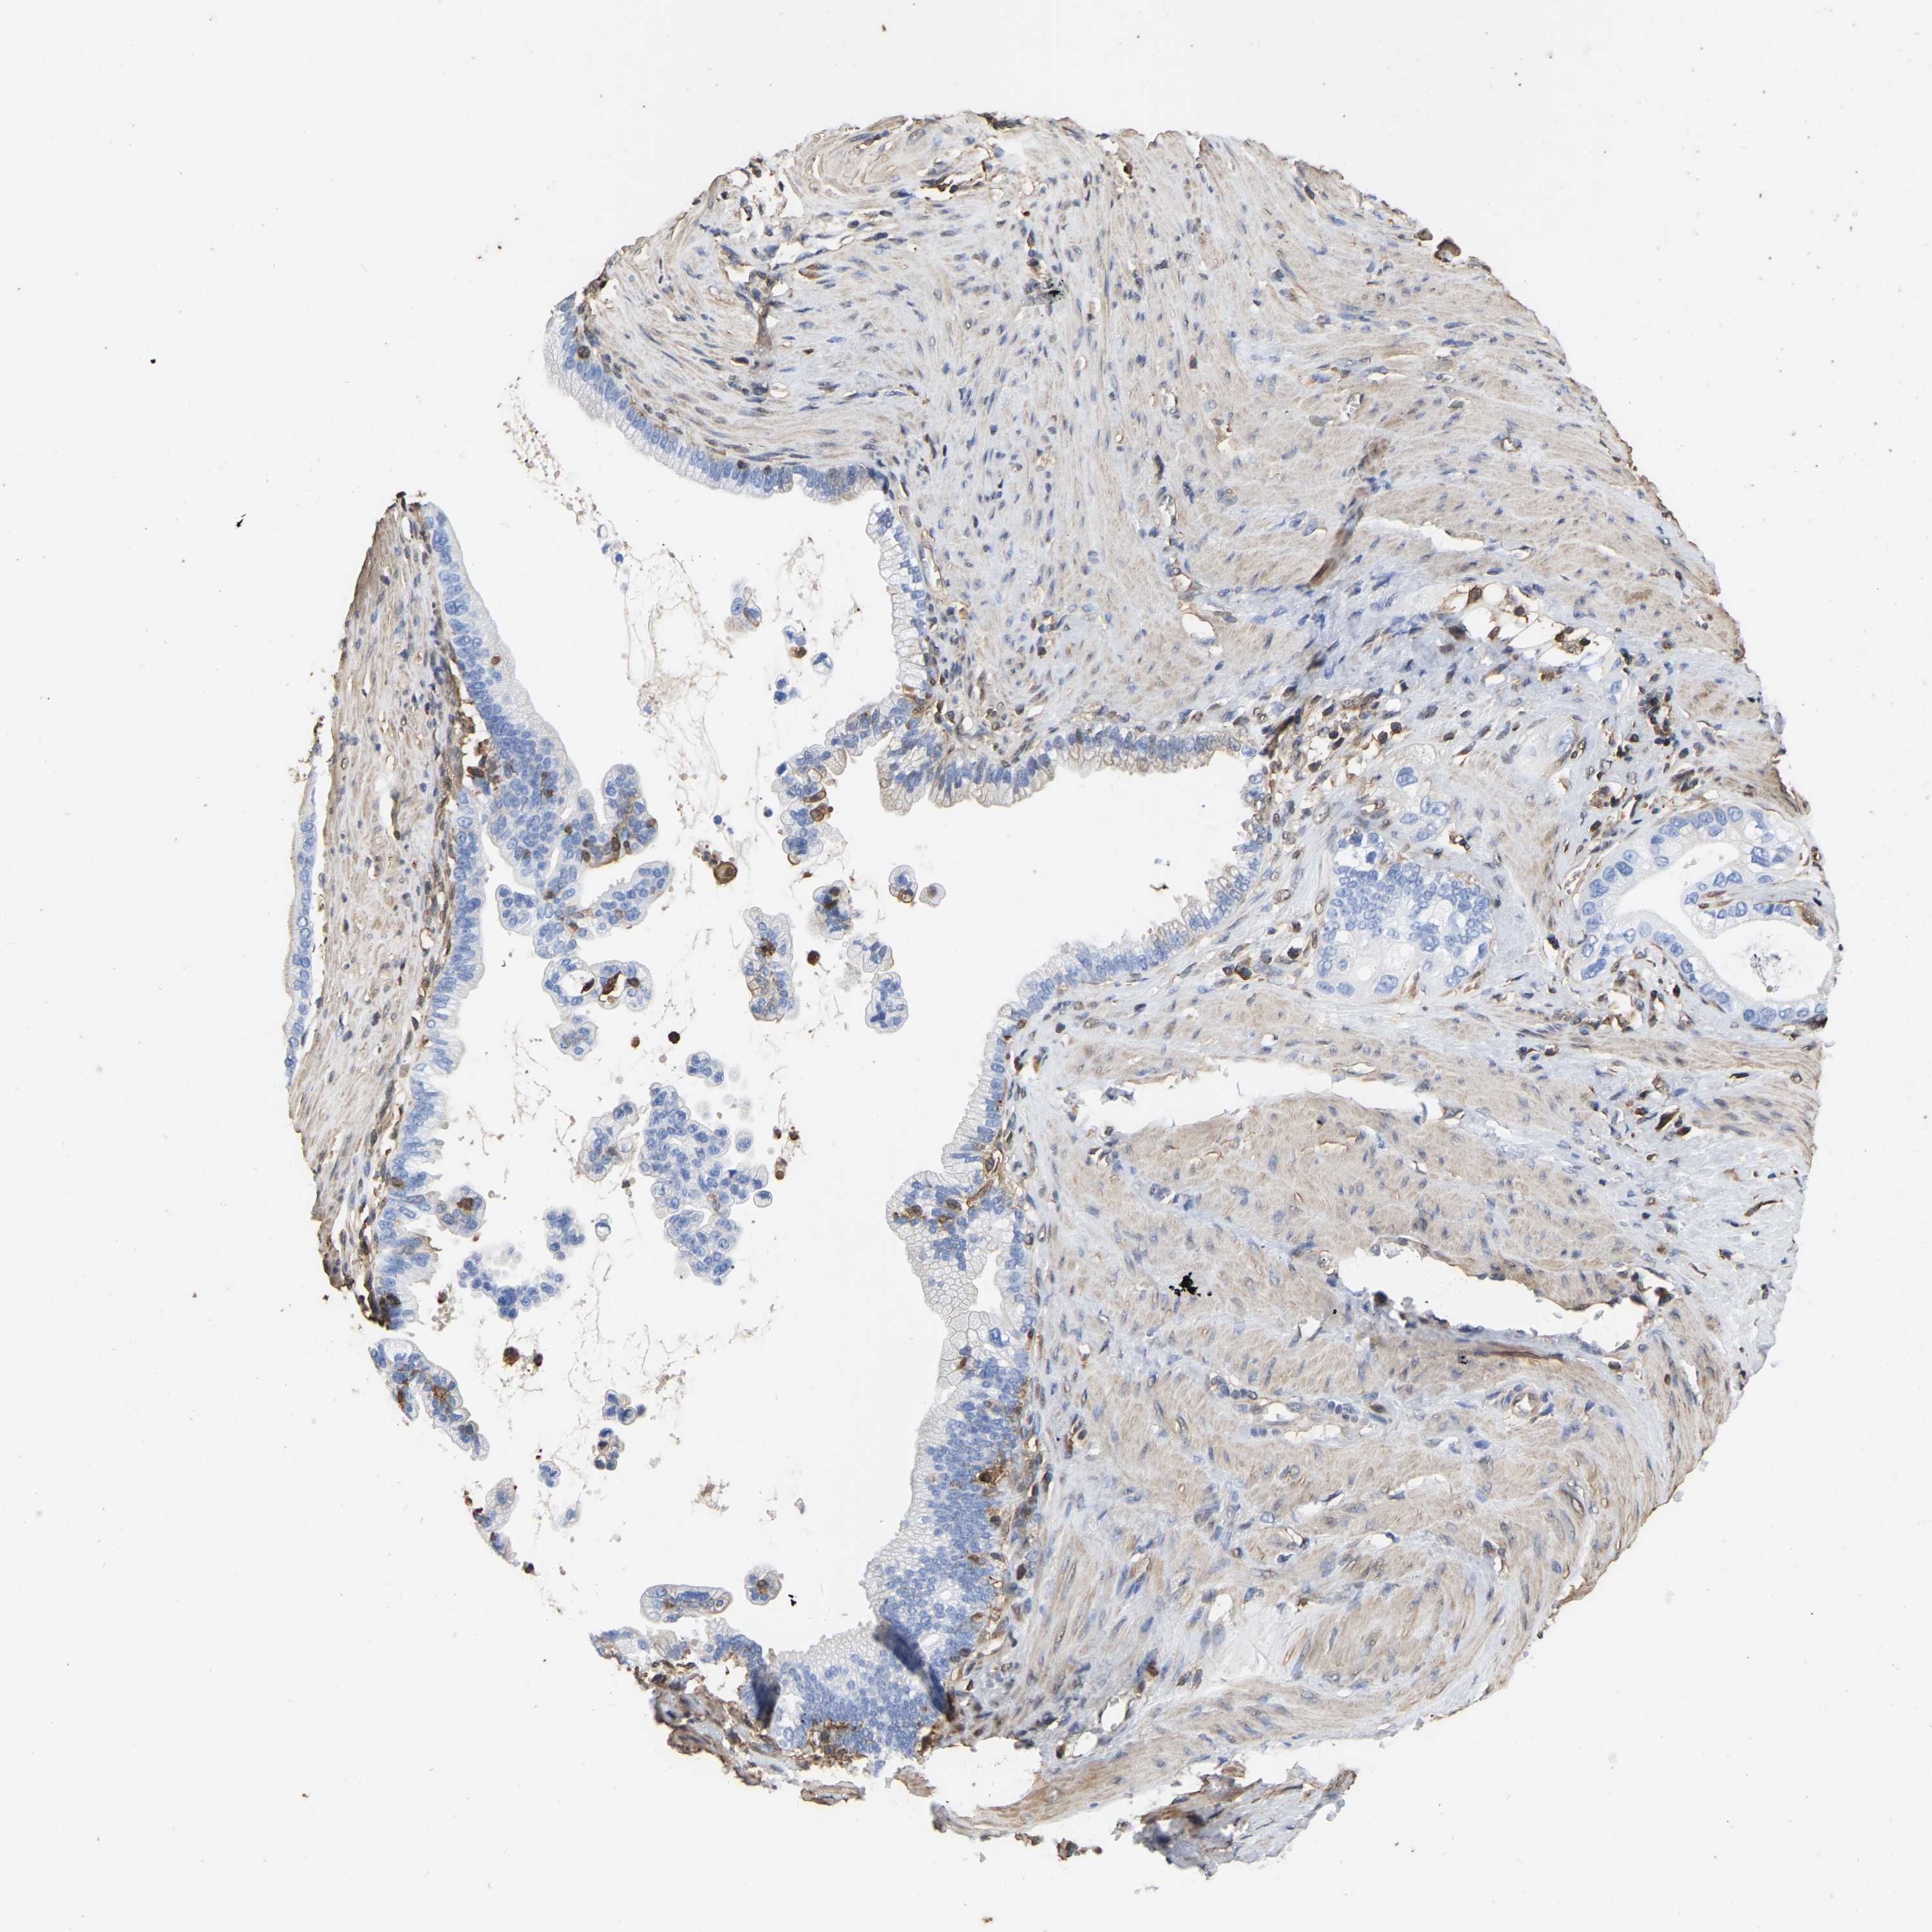

PANCREATIC CANCER - Protein expressioni

A mouse-over function shows sample information and annotation data. Click on an image to view it in a full screen mode. Samples can be filtered based on level of antibody staining by selecting one or several of the following categories: high, medium, low and not detected. The assay and annotation is described here.

Note that samples used for immunohistochemistry by the Human Protein Atlas do not correspond to samples in the TCGA dataset.

Antibody stainingi

Antibody staining in the annotated cell types in the current human tissue is reported as not detected, low, medium, or high, based on conventional immunohistochemistry profiling in selected tissues. This score is based on the combination of the staining intensity and fraction of stained cells.

Each image is clickable and will lead to virtual microscopy that enables deeper exploration of all samples and also displays staining intensity scores, fraction scores and subcellular localization as well as patient and tissue information for each sample.

Antibody HPA019007

Antibody CAB004641

Staining

High

Medium

Low

Not detected

Intensity

Strong

Moderate

Weak

Negative

Quantity

>75%

75%-25%

<25%

None

Location

Nuclear

Cytoplasmic/membranous

Cytoplasmic/membranous,nuclear

Adenocarcinoma, NOS

Adenocarcinoma, metastatic, NOS